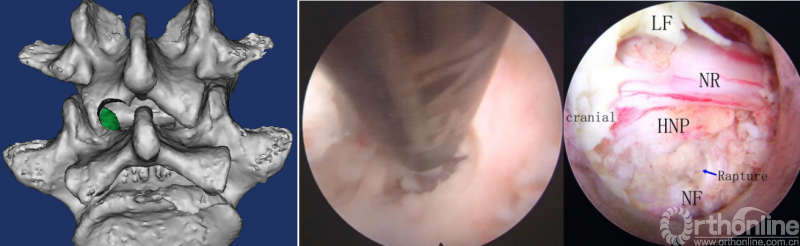

第五步“咬”:咬除部分上关节突,显露椎间盘及神经根;

第六步“切”:切除椎间盘;

第七步“旋”:旋转舌形套管保护神经根;